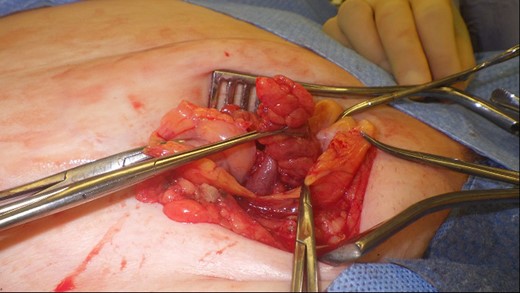

This 82-year-old lady presented with a sudden painful right sided groin swelling not previously noticed. She had no features of obstruction and was opening her bowels and not vomiting. Her medical background included left sided femoral hernia repair in 2005, coronary artery bypass graft and bilateral total knee replacements. On examination her abdomen was soft with the presence of a tender, irreducible swelling in the right groin, inferolateral to the pubic tubercle. She had good bowel sounds and there was stool present in the rectum on PR examination. A full set of blood tests demonstrated no abnormality. A CT abdomen and pelvis demonstrated an incarcerated right sided femoral hernia containing an 8 mm long inflamed appendix with a small amount of localized free fluid and inflammation indicative of De Garengeot’s hernia with underlying acute appendicitis (Fig. 1). The hernia sac diameter measured 2 mm on CT scan. She was taken to theatre for an open Lockwood repair of her femoral hernia and an appendicectomy. Following an initial Lockwood incision over the lump, dissection was performed down to the hernia sac also exposing the inguinal ligament (Fig. 2). The tightness of the femoral ring made mobilization of the appendix difficult. By partially incising the inguinal ligament superior to the femoral ring, the appendix was freed, and on inspection showed inflammation particularly towards the tip (Fig. 3). The caecum was then reduced and the inguinal ligament was repaired with non-absorbable suture. The femoral hernia was then repaired with a small funnel of ultrapro mesh. Appendicectomy was then performed in the usual fashion via the Lockwood incision leaving a slightly longer stump than usual (Fig. 4).

Vermiform appendix freed from hernial sac showing inflammation towards the tip.